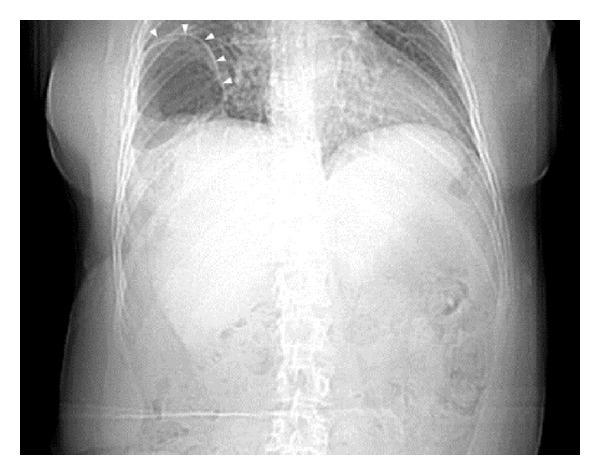

Traumatic diaphragmatic hernias are rare and challenging to diagnose. Following trauma, diagnosis may occur immediately or in a delayed fashion. It is believed that left traumatic diaphragmatic hernias are more common as a result of the protective right-sided anatomic lie of the liver. If unrecognized, traumatic diaphragmatic injuries are subject to enlarge over time as a result of the normal pressure changes observed between the thoracic and abdominal cavities. Additionally, abrupt changes to the pressure gradients, such as those which occur with positive pressure ventilation or surgical manipulation of the abdominal wall, can act as a nidus for making an asymptomatic hernia symptomatic. We report our experience with a delayed traumatic right-sided diaphragmatic hernia presenting with large bowel incarceration two months after abdominoplasty. In our review of the literature, we were unable to find any reports of delayed presentation of a traumatic right-sided diaphragmatic hernia occurring acutely following abdominoplasty.

创伤性膈疝较为罕见,诊断颇具挑战性。创伤后,诊断可能立即出现,也可能延迟出现。据信,由于肝脏位于右侧的解剖位置具有保护作用,左侧创伤性膈疝更为常见。若未被识别,创伤性膈肌损伤会因胸腔和腹腔之间正常的压力变化而随时间扩大。此外,压力梯度的突然变化,如正压通气或腹壁手术操作时发生的变化,可促使无症状疝出现症状。我们报告了一例在腹壁成形术后两个月出现大肠嵌顿的延迟性创伤性右侧膈疝的病例。在我们查阅文献时,未发现有任何关于腹壁成形术后急性出现延迟性创伤性右侧膈疝的报告。